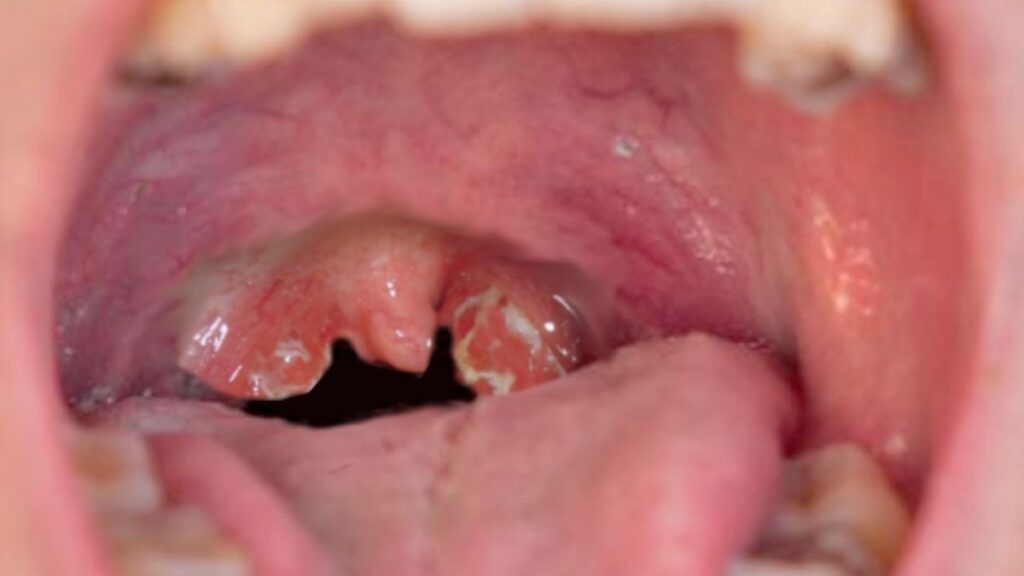

Tonsillitis is another frequent concern. It involves inflammation of the tonsils and can cause a sore throat, difficulty swallowing, and fever. Children with recurrent bouts may experience significant discomfort and missed school days.